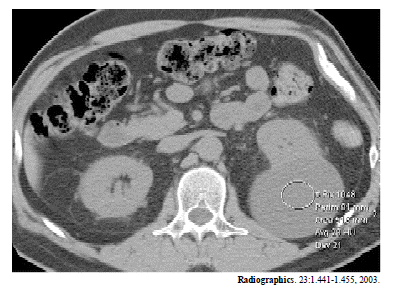

A figura acima mostra um corte de tomografia computadorizada de um homem com 47 anos de idade. Considerando essa imagem e as patologias a ela associadas, julgue os seguintes itens.

A melhor fase do contraste para avaliação de lesões parenquimatosas renais é a excretora.

A figura acima mostra um corte de tomografia computadorizada de um homem com 47 anos de idade. Considerando essa imagem e as patologias a ela associadas, julgue os seguintes itens.

O exame foi realizado com contraste venoso.

A figura acima mostra um corte de tomografia computadorizada de um homem com 47 anos de idade. Considerando essa imagem e as patologias a ela associadas, julgue os seguintes itens.

No rim esquerdo, há um cisto cortical com comportamento exofítico.

A figura acima mostra um corte de tomografia computadorizada de um homem com 47 anos de idade. Considerando essa imagem e as patologias a ela associadas, julgue os seguintes itens.

São visíveis adenomegalias para aórticas.